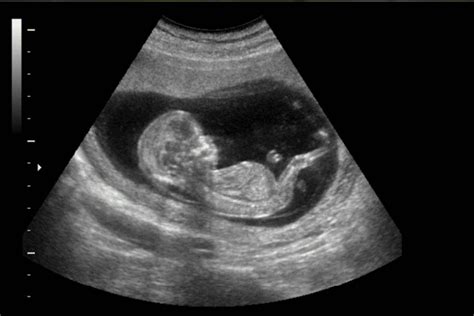

Le evidenze scientifiche che dimostrano la trasmissione delle emozioni materne al feto continuano ad accumularsi. Un caso emblematico è quello di un'ecografista in Oklahoma, USA, che ha catturato un filmato ecografico sorprendente. Durante una sessione di ecografia, la madre in attesa ha iniziato a ridere. L'ecografista ha notato immediatamente che il bambino sullo schermo si muoveva in risposta alle risate della madre. Questo ha generato un'atmosfera di gioia condivisa nella stanza, mentre tutti osservavano il bambino "rimbalzare" sullo schermo al ritmo delle risate materne. L'ecografista ha rassicurato che, nonostante l'apparenza sullo schermo dell'ecografo, ridere non arreca alcun danno al bambino, anzi, sembra stimolarlo positivamente.